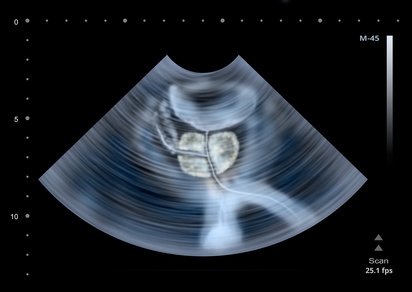

ProstatavergrößerungProstatavergrößerung – gutartig aber lästig von menscore 3. Juli 2016 Mit zunehmendem Alter wächst die Prostata. Ist dieser Vorgang gutartig, wird er benigne Prostatahyperplasie (BPH) genannt. Die Drüse beginnt zwar schon ab 30 zu wachsen, Beschwerden macht sie aber vor allem bei Männern ab 60. Weiterlesen